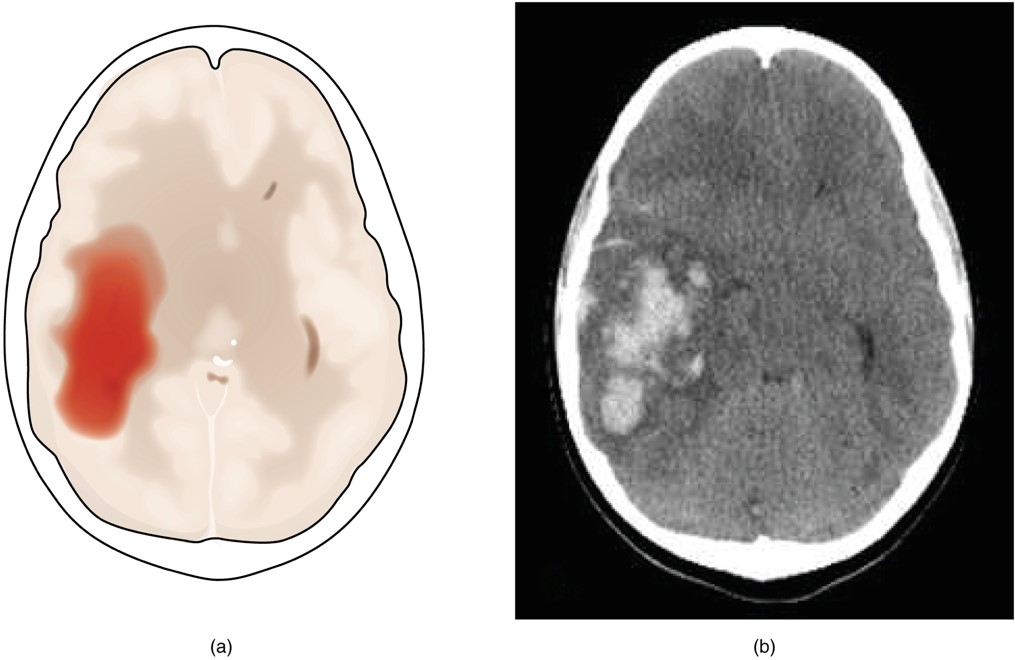

• Hemorrhagic stroke = bleeding into the brain because of a damaged blood vessel. Accumulated blood fills in a region of the cranial vault and presses against the tissue in the brain. This pooling blood causes secondary symptoms such as loss of function, pressure on neighboring arteries resulting in a larger damage area, potentially compromising the blood-brain barrier resulting in additional fluid on brain = edema.

Figure 16.3 Hemorrhagic Stroke (a) A hemorrhage into the tissue of the cerebrum results in a large accumulation of blood with an additional edema in the adjacent tissue. The hemorrhagic area causes the entire brain to be disfigured as suggested here by the lateral ventricles being squeezed into the opposite hemisphere. (b) A CT scan shows an intraparenchymal hemorrhage within the parietal lobe. (credit b: James Heilman)